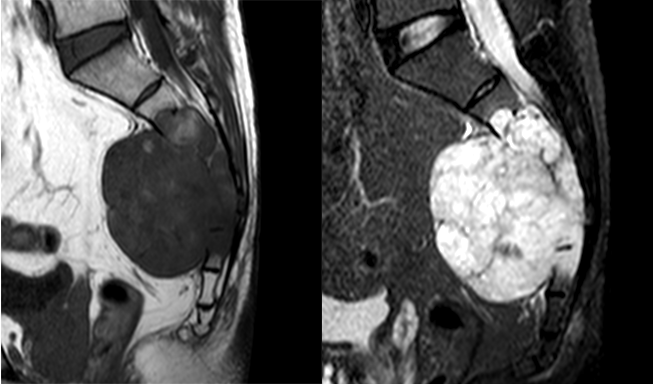

瘤软骨

瘤软骨为肿瘤细胞产生的软骨基质,多来源于软骨类肿瘤,或内有化生瘤软骨成分的其他肿瘤如成软骨型骨肉瘤。瘤软骨为软组织密度,未钙化时,主要通过 MRI 检查显示。由于瘤软骨多由富含水分及粘多糖的透明软骨构成,故 T1WI 呈偏低信号,T2WI 或 PDWI 呈明显高信号,被低信号的纤维间隔分开呈分叶状(图 24、图 25a-b),增强扫描多呈不均匀分隔状强化(图 25c),主要是纤维间隔强化,瘤软骨强化不明显之故。

图片

图 24.瘤软骨:内生软骨瘤

图 25.瘤软骨:内生软骨瘤